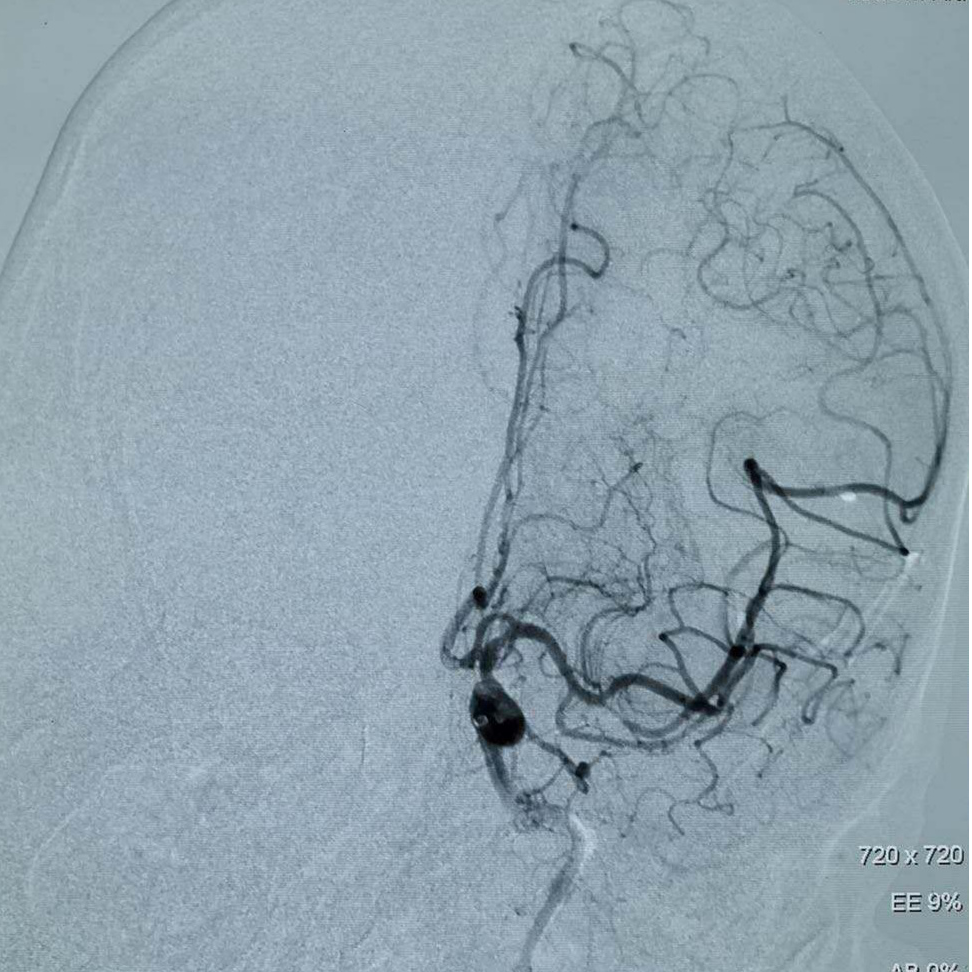

全脑血管造影术提示:左侧颈内动脉起始部闭塞,左侧颈内颅内段未见显影;在颈内动脉起始部采用Rebar-18微导管采用SWIM(支架取栓+抽吸)技术。

支架于血栓充分贴合后取栓系统回收,复查造影示:左侧大脑中动脉远端未见显影;Silverspeed14微导丝携带Rebar-18微导管到达左侧颈内动脉M2段,采用SWIM技术后复查造影血流通畅。

PT导丝携带颈动脉支架通过左侧颈内动脉狭窄处,释放支架后复查造影支架贴壁良好狭窄率不足10%。

术后复查左侧颈内动脉颅内段血供良好